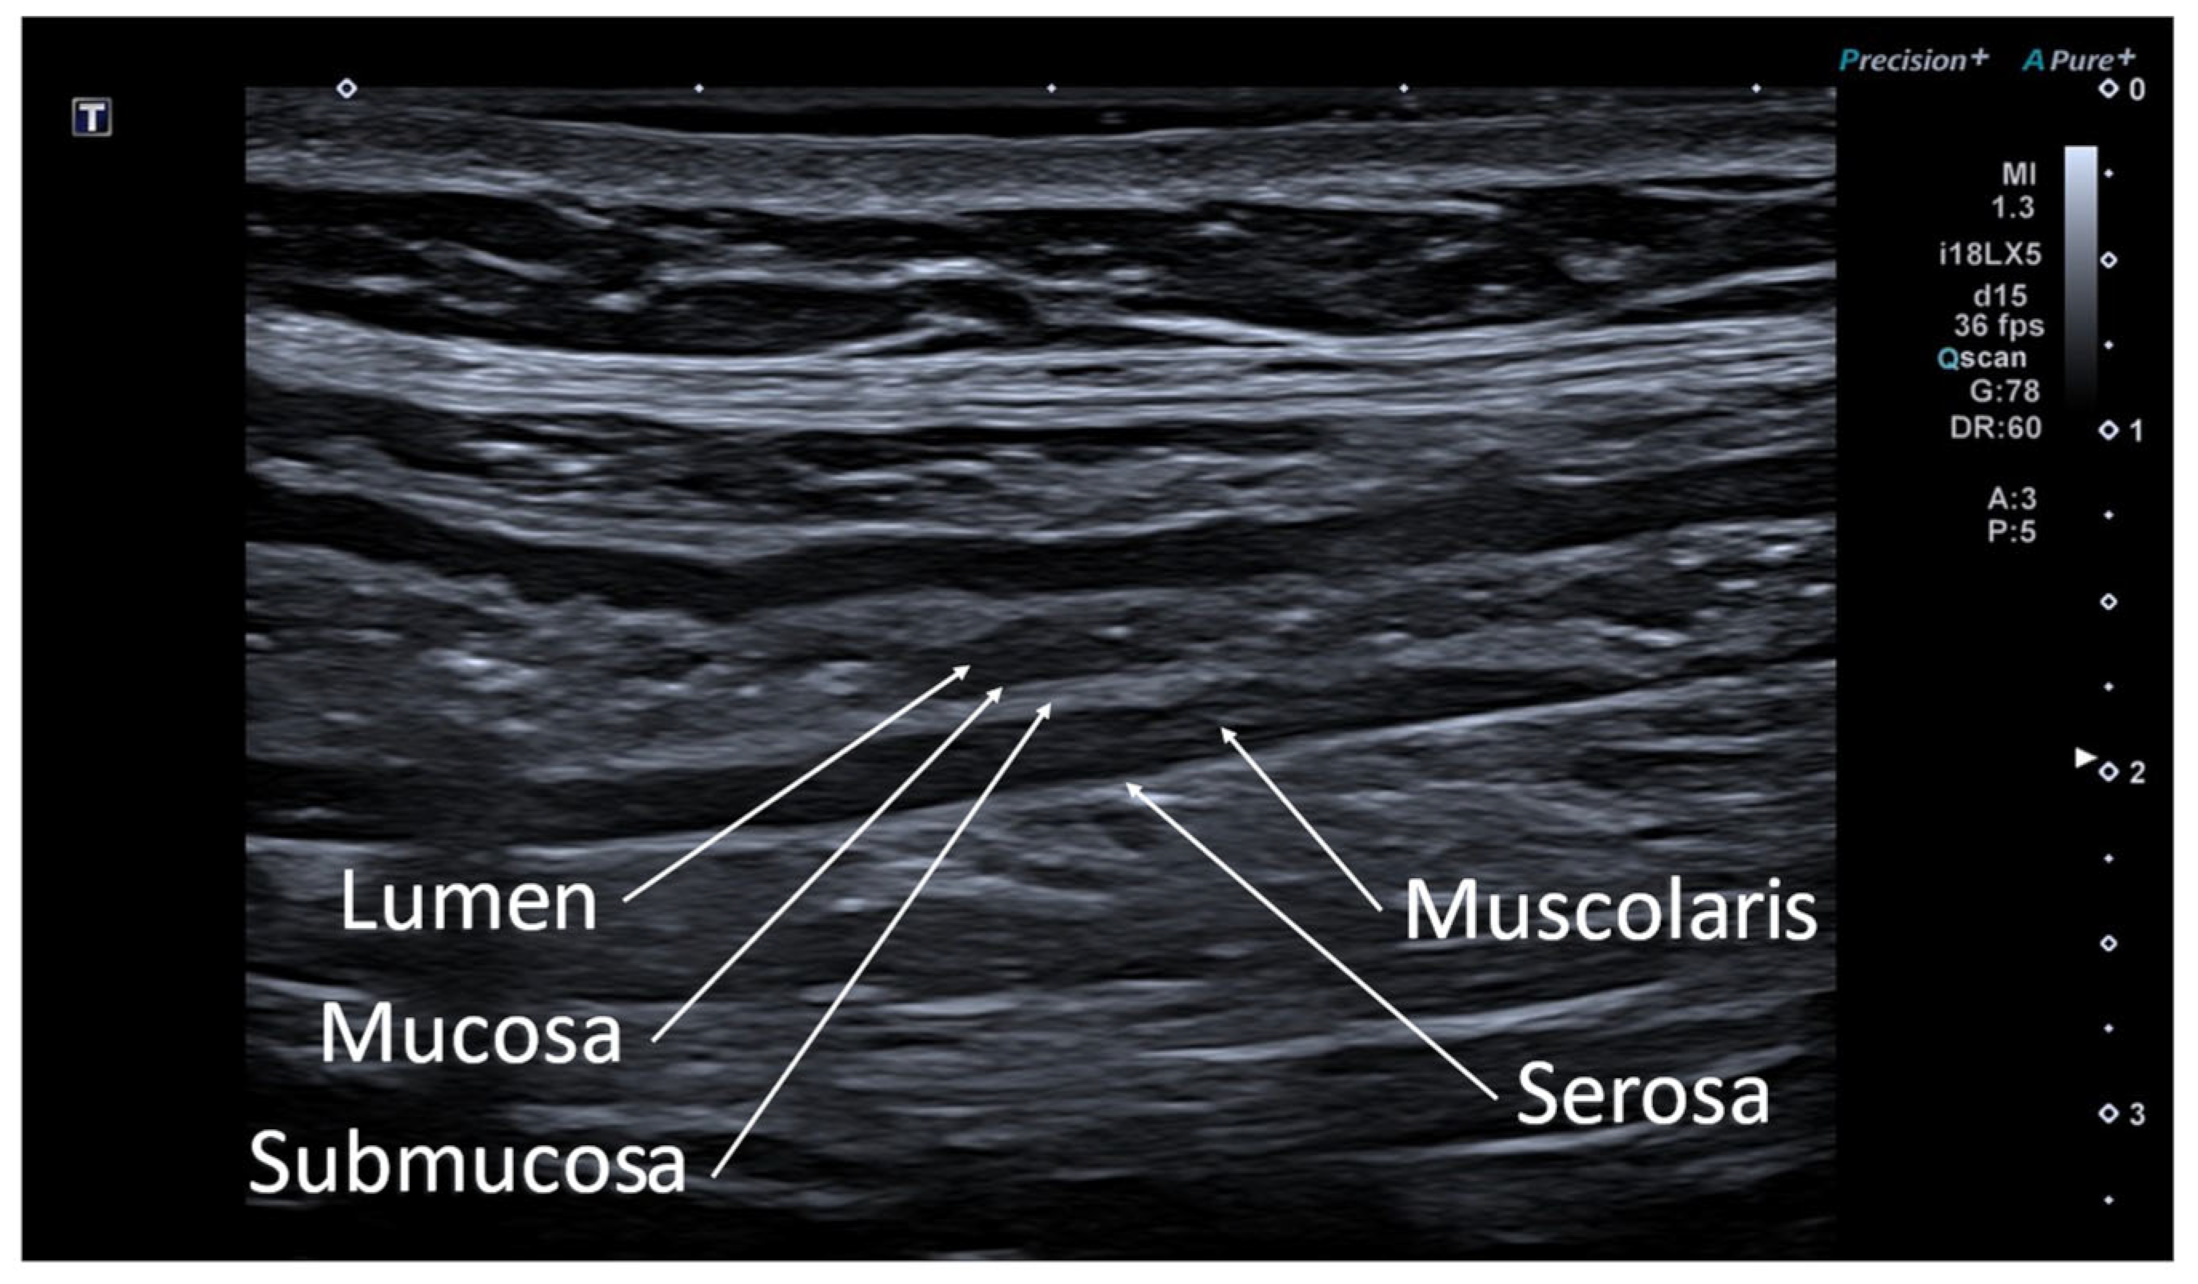

2. Ultrasonographic Anatomy of Gastrointestinal Tract